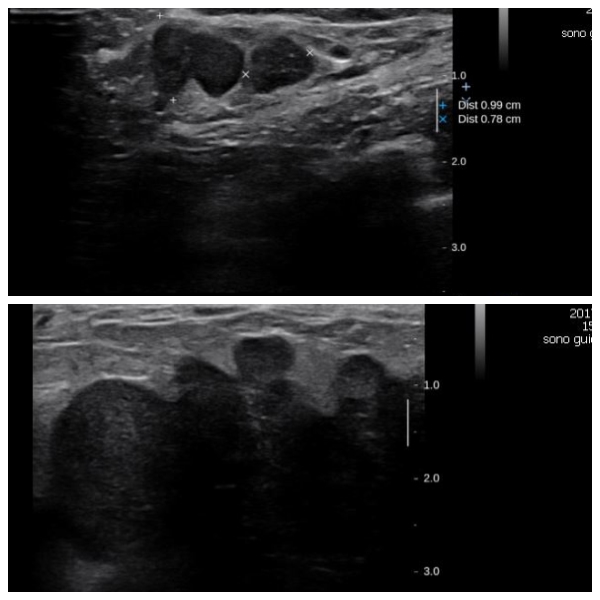

상기환자 좌측유방의 멍울로 내원하신 40대 여성분으로 좌측 유방전체에 분포된

의심스러운 멍울 조직검사 시행하여 좌측 침윤성 유관암 진단되었습니다.